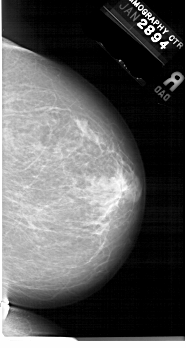

A_1679_1.LEFT_MLO

LEFT_MLO LINES 6781 PIXELS_PER_LINE 3631 BITS_PER_PIXEL 12 RESOLUTION 43.5 OVERLAY